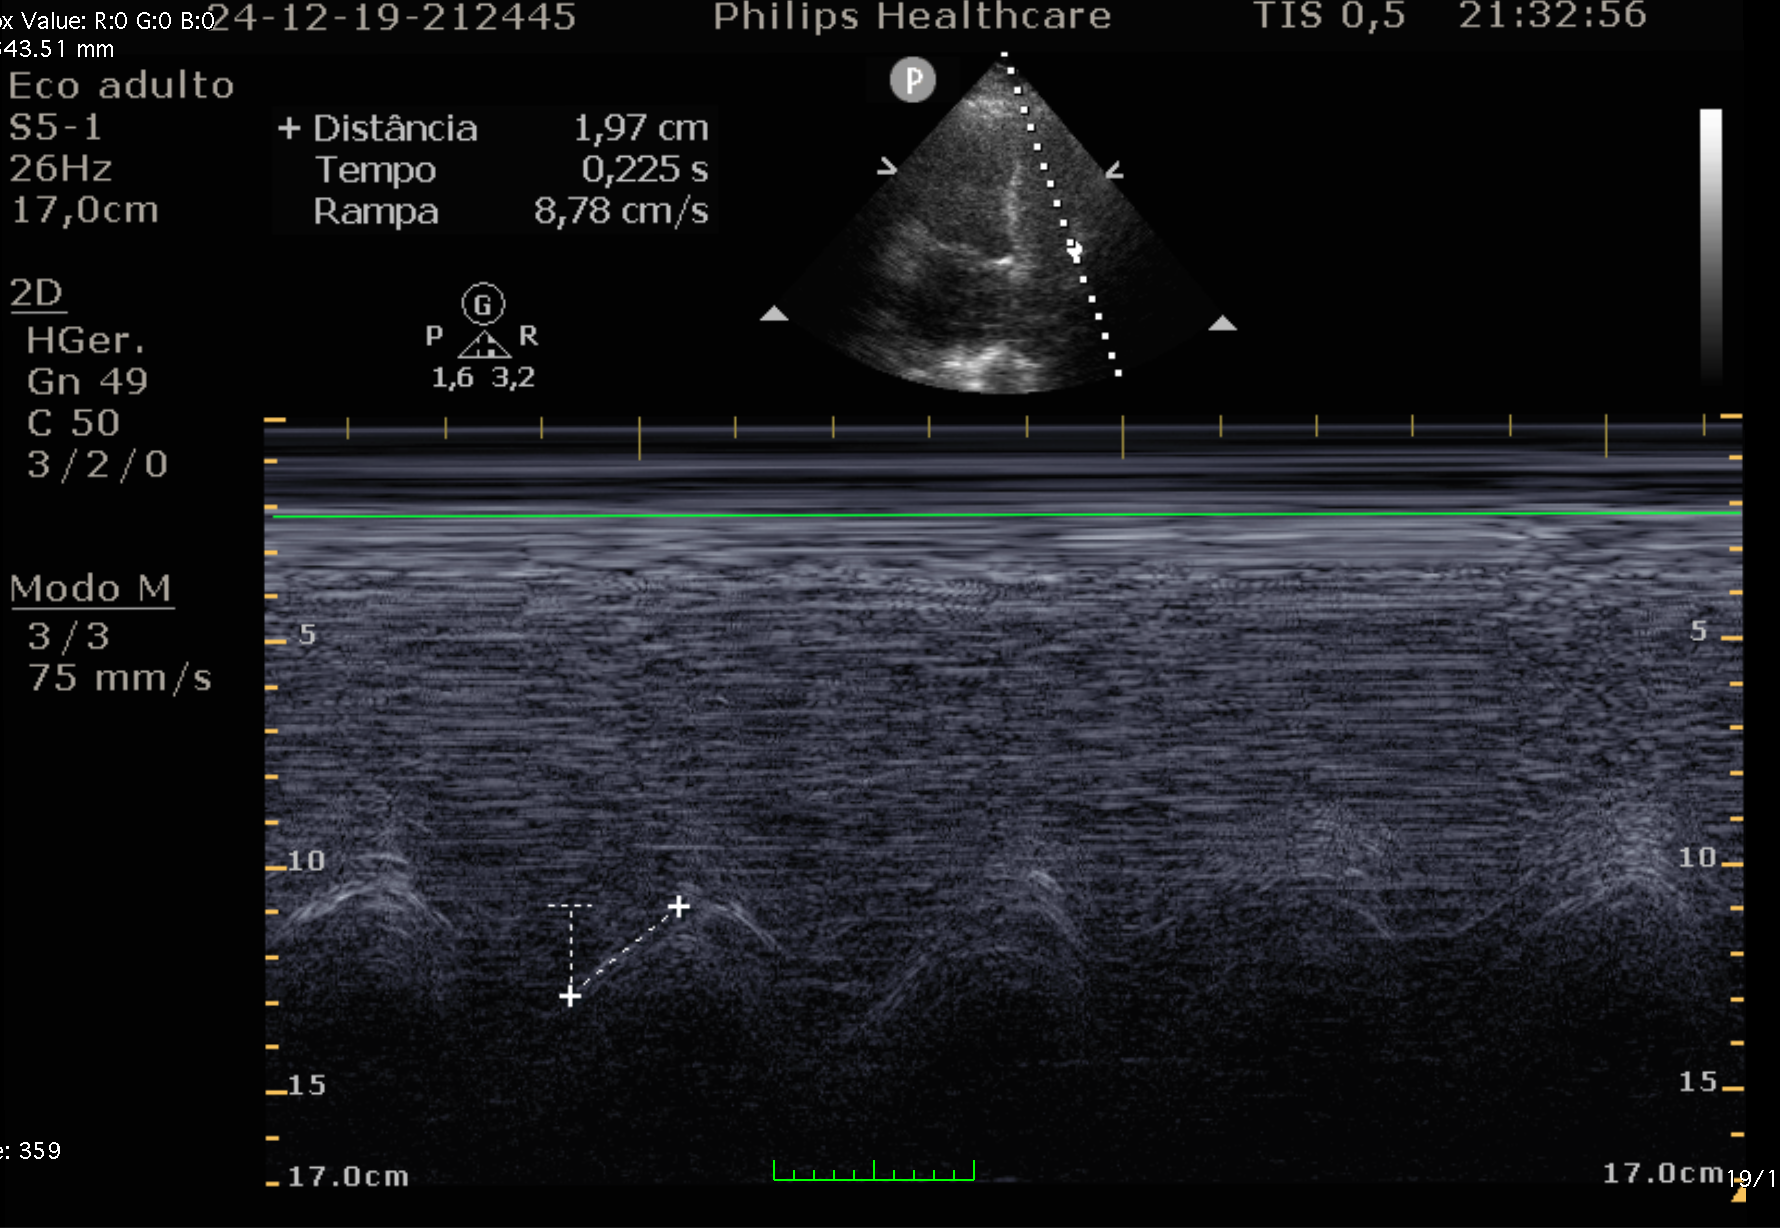

• Modo M ou 2D: Comparar excursão sistólica dos diferentes segmentos

• TAPSE: Frequentemente reduzido (≤ 17 mm) em TEP com disfunção de VD